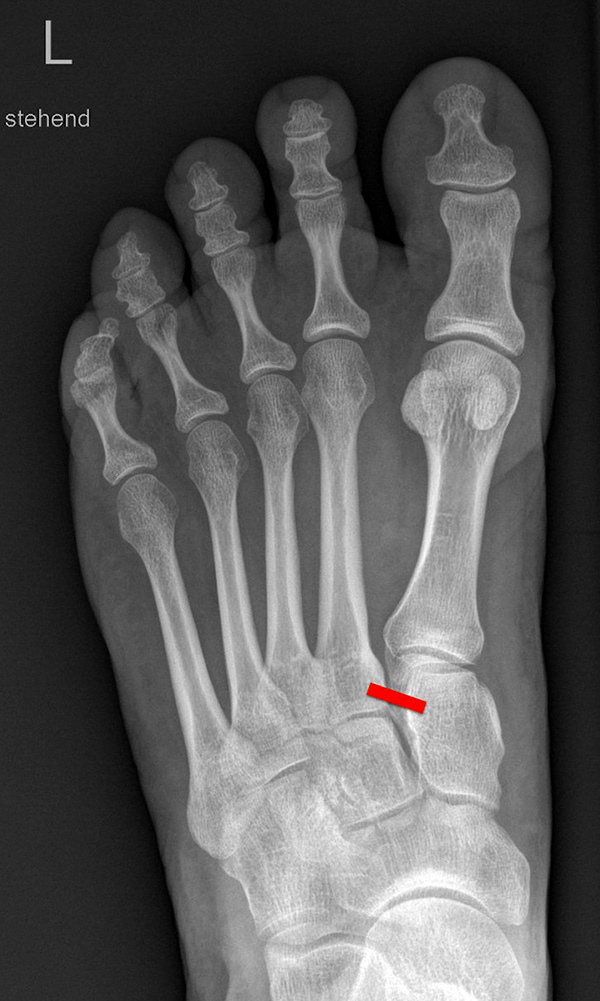

Standardisierte Röntgenaufnahmen des betroffenen Fußes, dorsoplantar (dp), streng seitlich sowie eine Schrägaufnahme werden angefertigt. Diese sollten möglichst unter Belastung angefertigt werden, da in den unbelasteten Aufnahmen insbesondere diskrete Veränderungen häufig nicht sicher zu erkennen sind.

Auf den dp-Aufnahmen sollte der mediale Rand der Metatarsale-2-Basis mit dem medialen Rand des Os cuneiforme intermedium eine homogene Linie ohne Stufenbildung bilden (Abb. 7+8). Außerdem ist auf den Abstand zwischen der Metatarsale-1- und -2-Basis zu achten. Dieser sollte nicht größer als 2 mm bzw. im Vergleich zur Gegenseite nicht mehr als 1 mm erweitert sein. In bis zu 90% der Fälle zeigt sich ein sogenanntes „Fleck sign“ (Abb. 9), ein knöchernes Fragment zwischen der Metararsale-1- und -2-Basis im Sinne eines knöchernen Ausrisses des Lisfranc-Ligaments an der Metatarsale-2-Basis 211936410. Oft liegen zusätzliche Frakturen der Metatarsalebasen oder der Tarsale vor, die ebenfalls identifiziert werden sollten. Bei jeder Mittelfußbasisfraktur sollte umgekehrt an eine Lisfranc-Verletzung gedacht werden.

Zum Lesen der Bildbeschreibung und zur Vollansicht bitte die Bilder anklicken.

In der Schrägaufnahme sollte der mediale Rand des Cuboids mit dem medialen Rand der Metatarsale-4-Basis eine homogene Linie bilden.

In der seitlichen Aufnahme ist auf Dislokationen und Subluxationen in den Tarsometatarsalgelenken sowie auf einen Verlust des Fußlängsgewölbes zu achten. Bei Instabilitäten des 1. Strahls bzw. Abflachung des Fußlängsgewölbes tritt in der Seitaufnahme die plantare Kontur des Os cuneiforme mediale tiefer im Vergleich zur Basis des Metatarsale 5. Darüber hinaus sollte die Cyma-Linie im Bereich des Chopartgelenkes in der Seitaufnahme eine harmonische S-förmige Linie bilden.